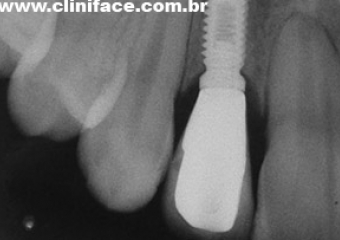

Imagens de implantes em incisivo lateral direito e esquerdo instalados